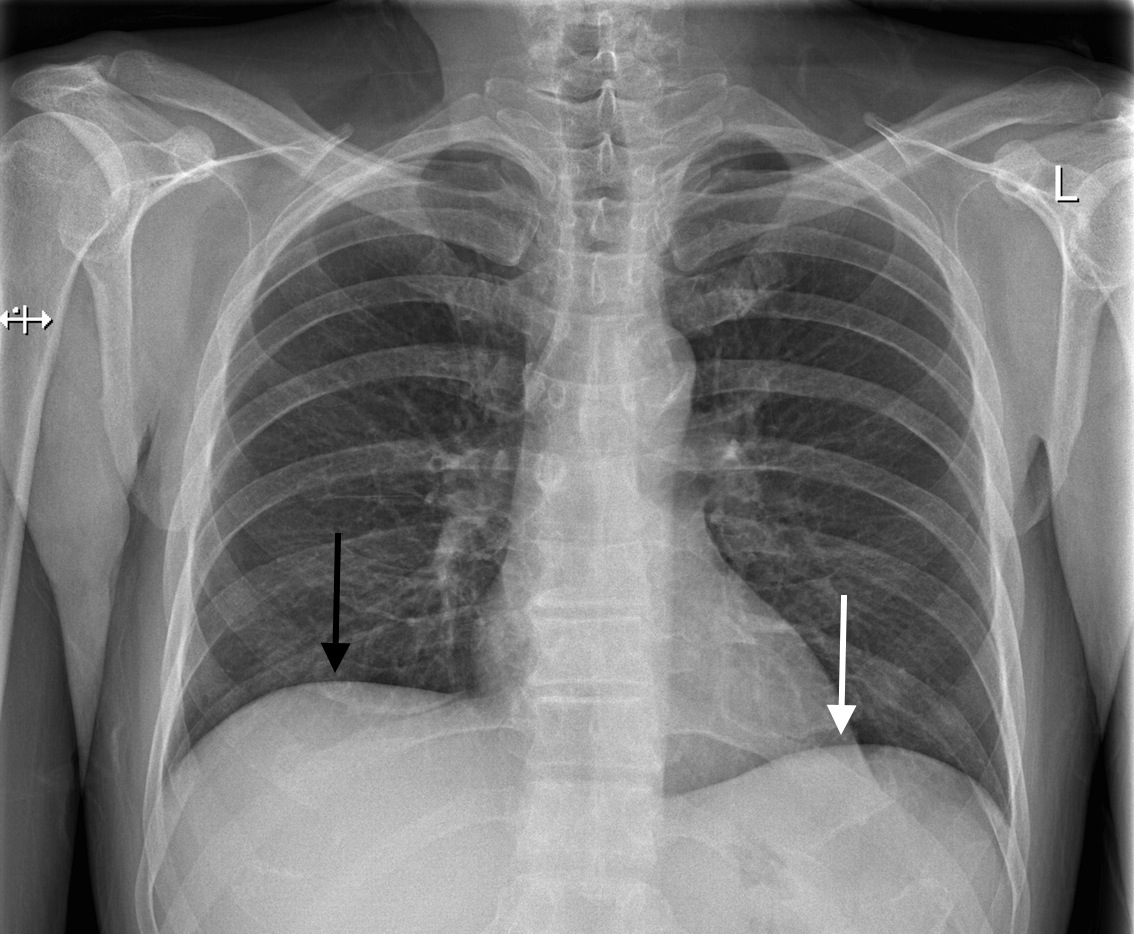

Radiological Anatomy Diaphragm Stepwards